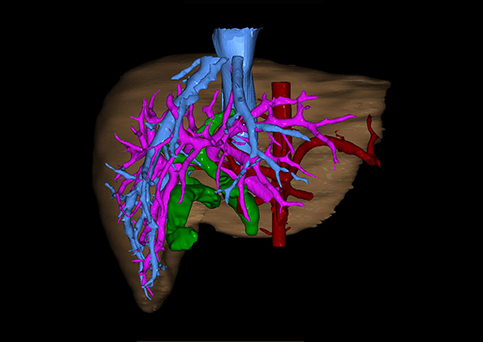

10、三维重建虚拟肝脏、胆道显像技术

三维虚拟肝脏技术是在二维影像学资料如CT等图像的基础上,通过三维重组软件和工具,比如青岛大学附属医院与海信医疗集团联合自主研发的海信计算机辅助手术系统(Hisense Computer Assisted Surgery,Hisense CAS),目前已投入临床并指导实际应用,利用该类系统对二维影像学的数据资料进行三维立体分析,重组形成立体的、有空间结构的、虚拟的肝脏三维图像。这项技术较传统的二维平面成像技术,有着明显的优势,3D虚拟肝脏技术可以构造出一个虚拟的、可视化的肝脏模型。通过对这种模型的观察,可以很容易地分辨出肝脏器官的组织结构、解剖特点,直观研究肝外胆总管的形态差异,明确肝内胆管的形态、走形、是否合并扩张、狭窄及结石,胰胆管合流的形态及共同通道内是否有狭窄、扩张和结石等病变情况,预先规划处理可能合并存在的肝内胆管扩张、狭窄或其他复杂胆道畸形,清晰地显示肝内脉管系统,包括门静脉、肝动脉及肝静脉的走行、分支,并可多角度、全方位观察病变胆道与其周围重要血管尤其是伴行的门静脉之间的解剖关系,大大提高了外科医师在术前对肝脏内部各管道结构及其变异判断的精确性和可靠性,精准地对病变进行判断和评估,还可根据患者自身的病变特点,制定出合理、个体化的手术方案,最大限度地降低术中和术后并发症发生率,并术中导航实时指导手术,提高手术的精准性和成功率。

图11:先天性胆管扩张症梭状型三维重建虚拟肝脏、胆道显像

a 图为术前二维CT扫描图像,箭头指示肝内胆管扩张;b 图为CT经多平面重组技术(MPR)所得的重建图像,可粗略地判断病变胆管的位置;c 图示术前Hisense CAS三维重建清晰显示胆管的病理形态及其与肝内三套血管系统的解剖关系;d 图示胆道系统与其伴行的门静脉系统的空间解剖关系;e 图为胆道系统立体形态,箭头处指示迷走胆管,源自肝脏直接汇入胆总管。术前规划先将迷走胆管与肝总管吻合成形,再行肝总管空肠Roux-en-Y吻合术。